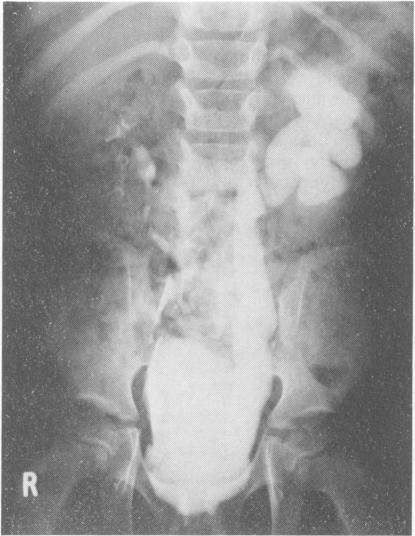

The association between spinal dysraphism and a neuropathic bladder is well known, but the diagnosis of the spinal lesion and the associated renal problems is often delayed. Four children referred with orthopaedic problems and in whom the bladder abnormally proved to be the major disability are described. Despite widely differing vertebral involvement, all had lower motor neurone neurological deficits confined to lumbar and upper sacral segments. All had unstable, variably thickened, small bladders, and it is proposed that the bladder abnormality is the result of a partial lesion of lumbosacral innervation, and not of an upper motor neurone lesion.

脊髓发育异常与神经源性膀胱之间的关联已为人熟知,但脊髓病变及相关肾脏问题的诊断常常延迟。本文描述了4例因骨科问题前来就诊的儿童,经证实膀胱异常是其主要致残因素。尽管椎体受累情况差异很大,但所有患儿均有局限于腰段和上骶段的下运动神经元神经功能缺损。所有患儿的膀胱均不稳定、厚度不一且较小,本文认为膀胱异常是腰骶部神经支配部分损伤的结果,而非上运动神经元损伤所致。